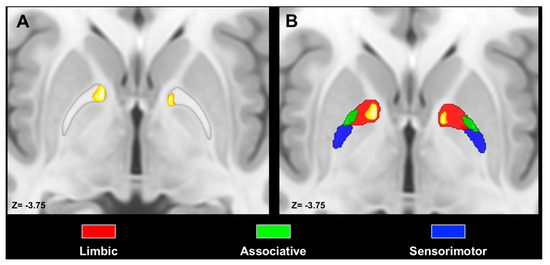

- Bertino, S.; Basile, G.A.; Bramanti, A.; Anastasi, G.P.; Quartarone, A.; Milardi, D.; Cacciola, A. Spatially coherent and topographically organized pathways of the human globus pallidus. Hum. Brain Mapp. 2020. [Google Scholar] [CrossRef]